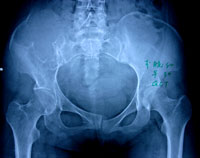

症状主要表现为不同程度的疼痛,可伴有肿胀、活动受限,病程从数周至数月不等,无特异性表现,不易从症状方面与其他骨肿瘤区别。骨巨细胞瘤多为单发病变,常见部位是长骨的骨端,最常见的部位是股骨远瑞、胫骨近端、桡骨远端,也可见于骶骨、胫骨远端、肱骨近端,股骨近端和腓骨近端。偶见于手及足部的小骨、胸腰段的椎体和肋骨。

X线平片 对于骨巨细胞瘤的影像学检查, X 线平片是最具诊断价值的放射学检查手段。骨巨细胞瘤在X 线片上表现为骨端的溶骨性破坏,可侵及干骺端,向关节侧延伸侵及部分或全部邻近关节软骨下的骨皮

质。肿瘤大小与发生病变骨的大小有关。肿瘤延患肢骨长轴侵及的范围往往小于延横轴侵及的范围,在骨干侧可见筛孔样改变,而在骨端的周围可见明显的骨皮质膨胀、变薄。病变内部为不同程度的溶骨改变,皮质外多没有骨膜反应;当出现病理骨折时则可见骨膜反应。通常可见到骨膜下新生骨有中断,骨膜保持完整,病变的松质骨边缘部分可有明显的界限。骨巨细胞瘤没有肿瘤基质的矿物化,关节渗出少见,但经常伴有病理性骨折发生。长骨以外部位的骨巨细胞瘤在X 线片上无特征性表现,与其他溶骨病变没有区别。